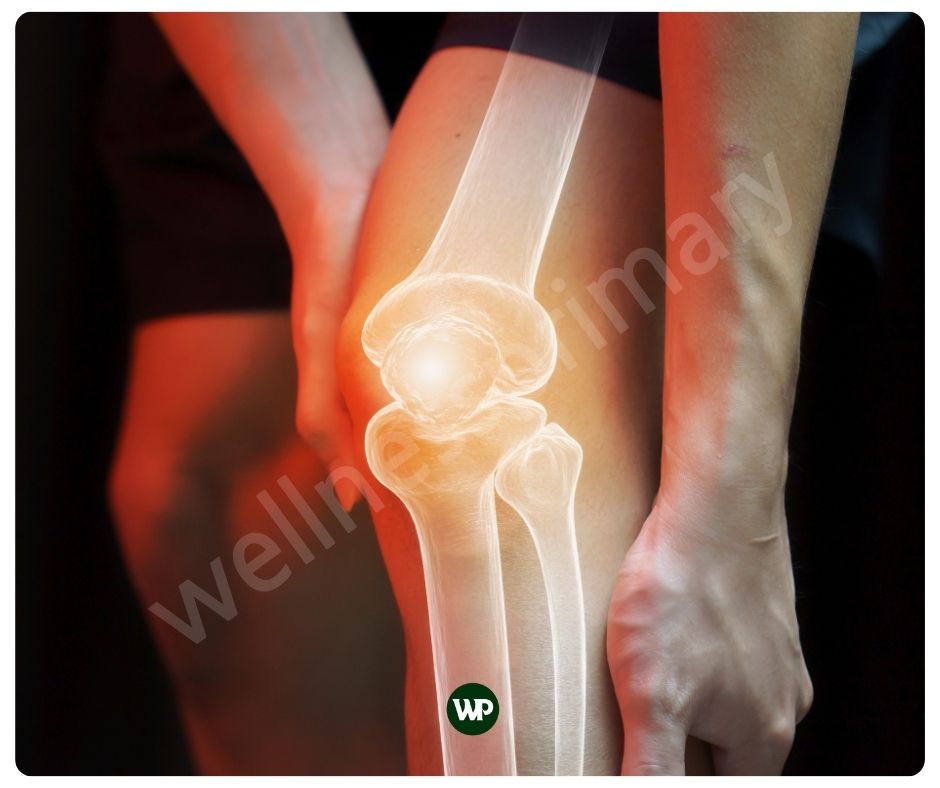

연골은 관절의 움직임을 부드럽게 하고 충격을 흡수하는 역할을 하는데요. 이러한 연골의 역할은 관절이 원활하게 움직이는데 중요하지요. 콘드로이친 효능은 위에서도 언급하였 듯이 연골 조직에 존재하며 연골 내부의 구조를 강화하고 유지하는 데 도움을 주어 관절 건강에 도움을 줍니다. 또한 콘드로이친은 관절의 윤활을 증진시켜, 움직임 시 마찰과 통증을 줄여주어 관절이 부드럽게 움직일 수 있도록 도와줄 수 있습니다.

관절염과 같은 염증은 연골을 파괴할 수 있는데요. 콘드로이친은 염증을 유발하는 화학물질의 생성을 억제하며, 이로 인해 관절염과 같은 염증성 질환에서 발생하는 통증과 부기를 감소시켜 줄 뿐 아니라 연골의 파괴도 막아줄 수 있습니다. 또한 염증이 감소함으로써 관절 통증을 완화하는 데 도움을 줍니다.

콘드로이친은 통증을 완화해 주고 관절에 윤활을 향상시키는 효과가 있습니다. 관절의 움직임이 더 편해지면서 운동 시의 편안함과 운동 능력을 증진시켜줄 수 있습니다. 또한 거동이 불편하신 분들께는 일상 생활의 활동 능력 향상에 도움을 줄 수 있습니다. 일상의 활동능력과 운동 능력을 증진해 줌으로써 운동을 통해 근육을 만드는데에도 도움이 될 수 있습니다.